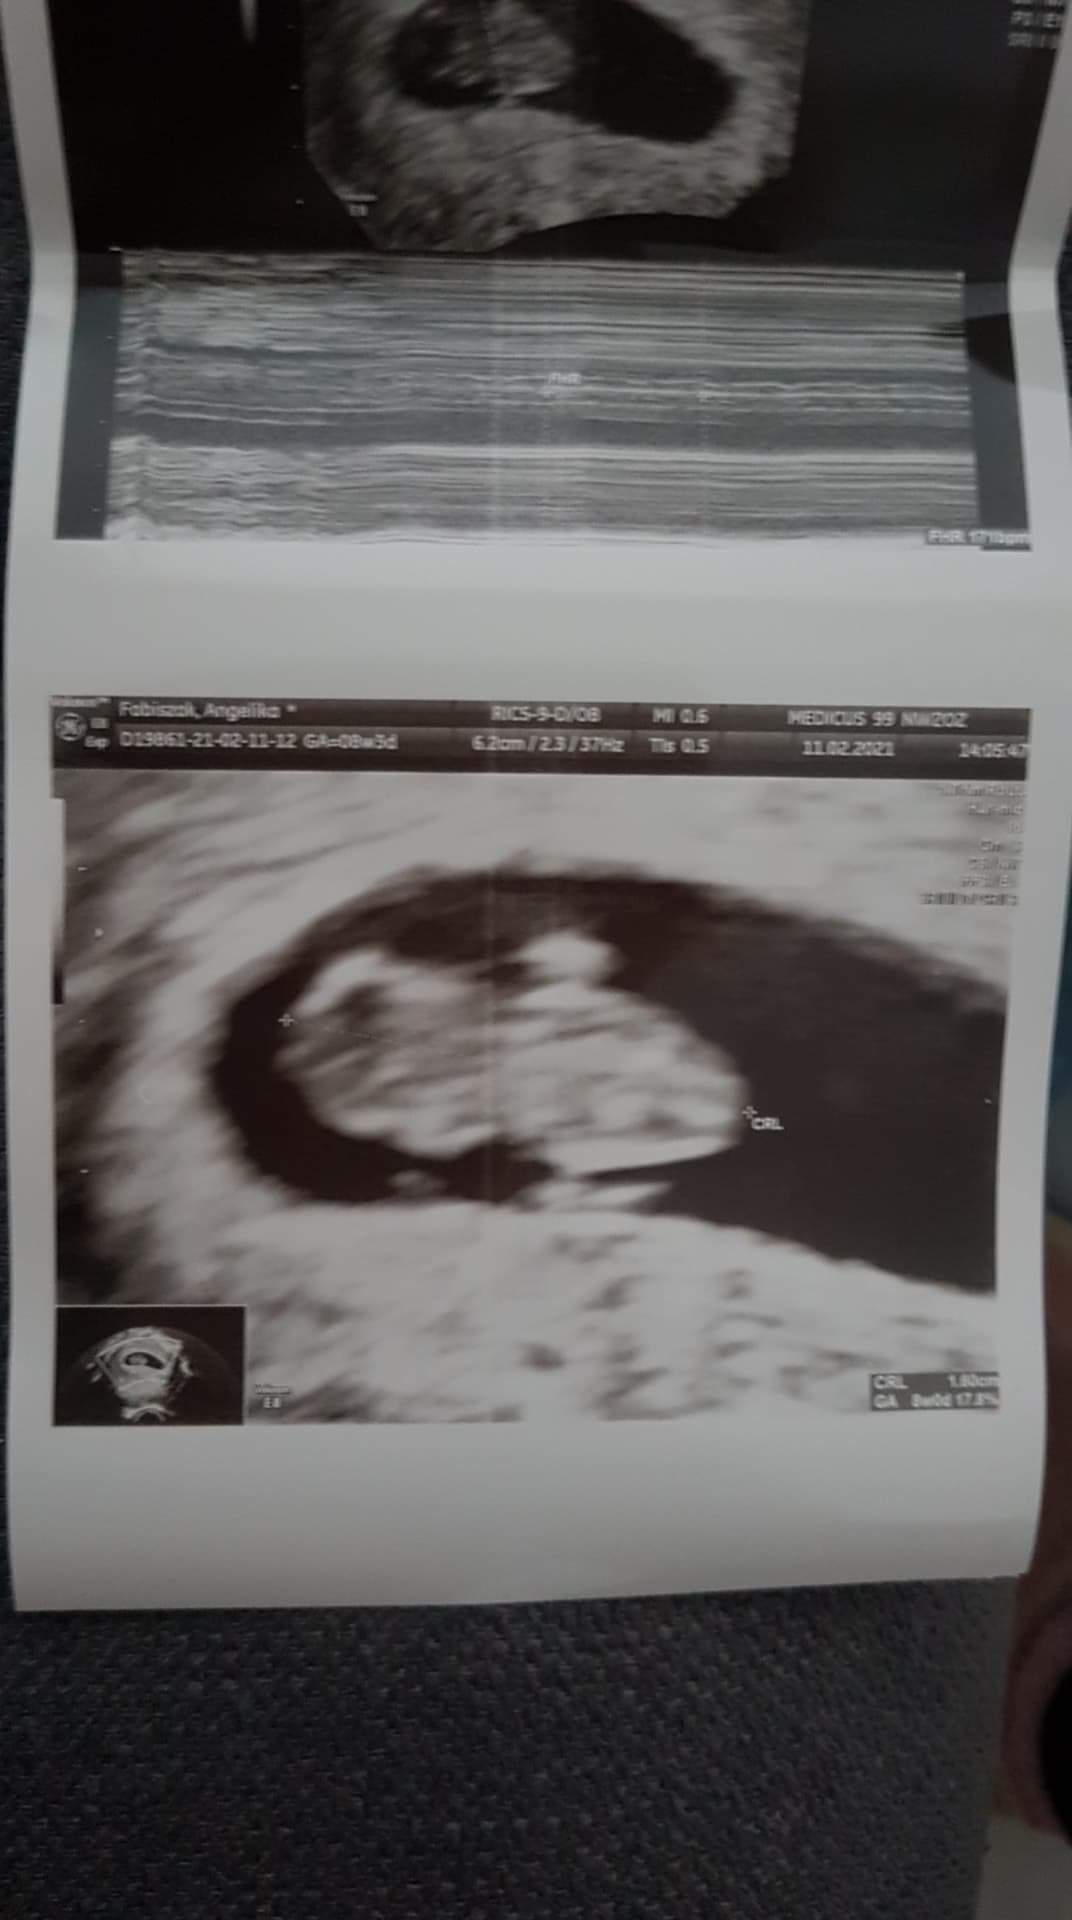

Dziewczyny po wizycie wszytsko okej! ♥

Ciąża pojedyncza. Jak powiedziałam doktorowi ze mam siostrę bliźniaczkę, a narzeczony mamę bliźniaczkę to powiedział o kurde to sprawdzę jeszcze raz 🤣

Wg Om 8+3 Wg usg rowne 8 ;)

Tętno 171/min wielkość 1,6 cm :)

Zobacz załącznik 1237198